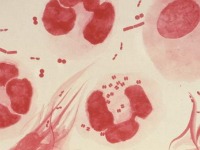

Expertos hallan primera cepa de gonorrea calificada de 'superbacteria'

Científicos hallaron en Japón una cepa de una "superbacteria" de la gonorrea que es resistente a todos los antibióticos recomendados y que podría transformar la infección que suele ser fácilmente tratable en una amenaza...